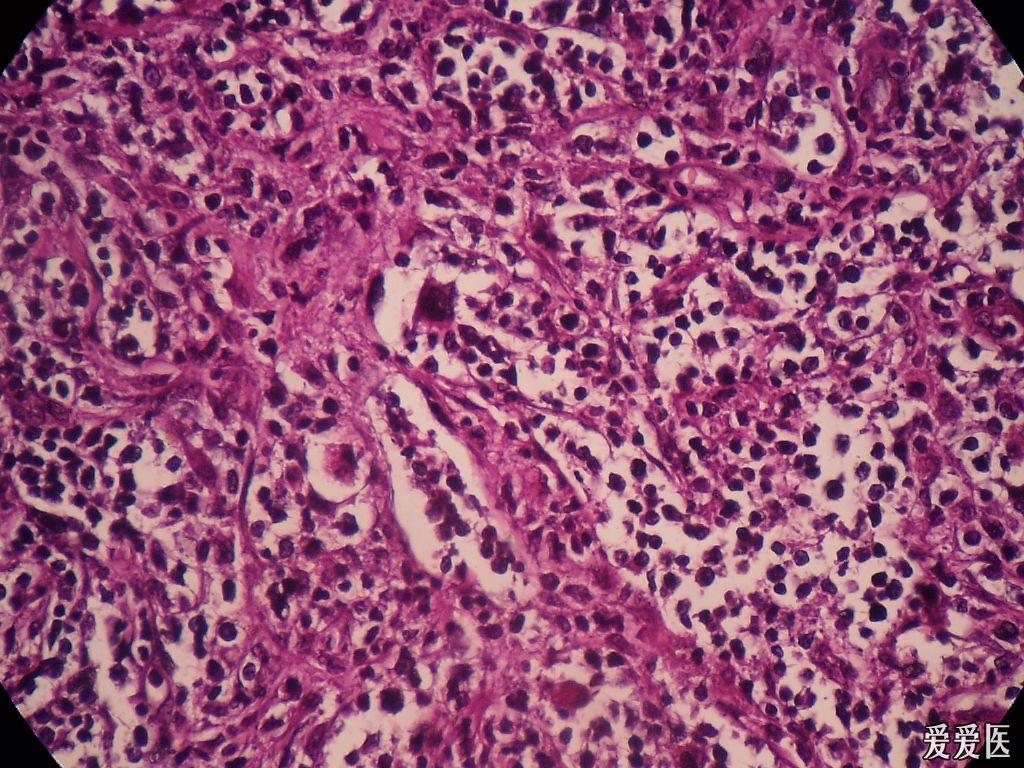

显微镜下的非霍奇金淋巴瘤